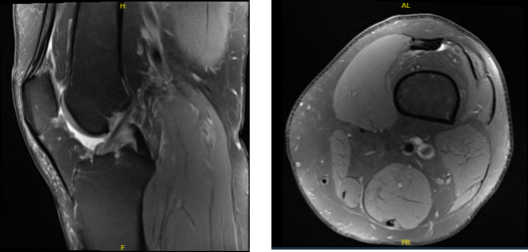

MRI presented after a week, and found medial meniscal tear with dominant radial component posterior horn with peripheral extrusion.

Osteoarthrosis with moderate to high-grade cartilage loss peripheral aspect of the medial compartment and a focal 3.5 x 14 mm moderate to high-grade cartilage defect along the lateral trochlear cartilage. Indeterminate lesion distal femur likely a probable enchondroma and small joint effusion were found.

Upon examination of the left knee, the patient is tender to palpation along the lateral joint line, and has an effusion. Patient also has PF crepitus and tenderness on palpation along the medial and lateral PF joint line. Patellar grinding test is positive.